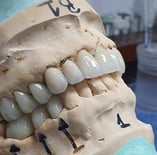

Coroa sobre Implante aparafusada em Modelo impresso. zirconia/cerâmica

Fase de produção laboratórial das coroas sobre dentes e implantes e facetas de porcelanas personalizadas

Em um bom laboratório, essas peças são confeccionadas com precisão, utilizando tecnologia avançada para garantir o ajuste perfeito e a estética desejada.